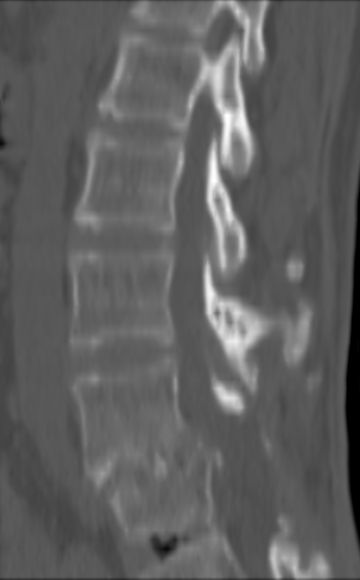

以下是引用余辉在2007-9-4 21:00:00的发言:[br]椎体棘突有点异常(像是被切割了),不知有否手术史,如椎体融合术等。单纯的退行性变可以出现椎间隙变窄,但同时一般会出现椎体上下缘的硬化增生,且椎体间完全融合的机率更小,本例椎体完全融合且椎体上下皮质缘破坏掉了,如果没有手术史,就应该考虑椎间盘炎性病变了,且椎体棘突及棘间韧带的变化也并不是不支持这个,多数小关节也融合了,且其形态也容易让人联想到如强脊炎及类风关等病变。[br][br][本贴已被 余辉 于 2007-9-4 21:03:55 修改过]

以下是引用chry3在2007-9-4 20:42:00的发言:[br]椎间盘病史?是什么样的病史,无双下肢放射痛,那就不是椎间盘突出了。是感染、什么性质的?[br]从图象看椎间隙消失,椎间盘组织未见,锥体滑脱是因为椎间盘溶解造成的[br]l4、5椎体骨质结构未见异常,l5上缘是l4的长期压迫所致[br]还是考虑椎间盘感染,结核。[br]